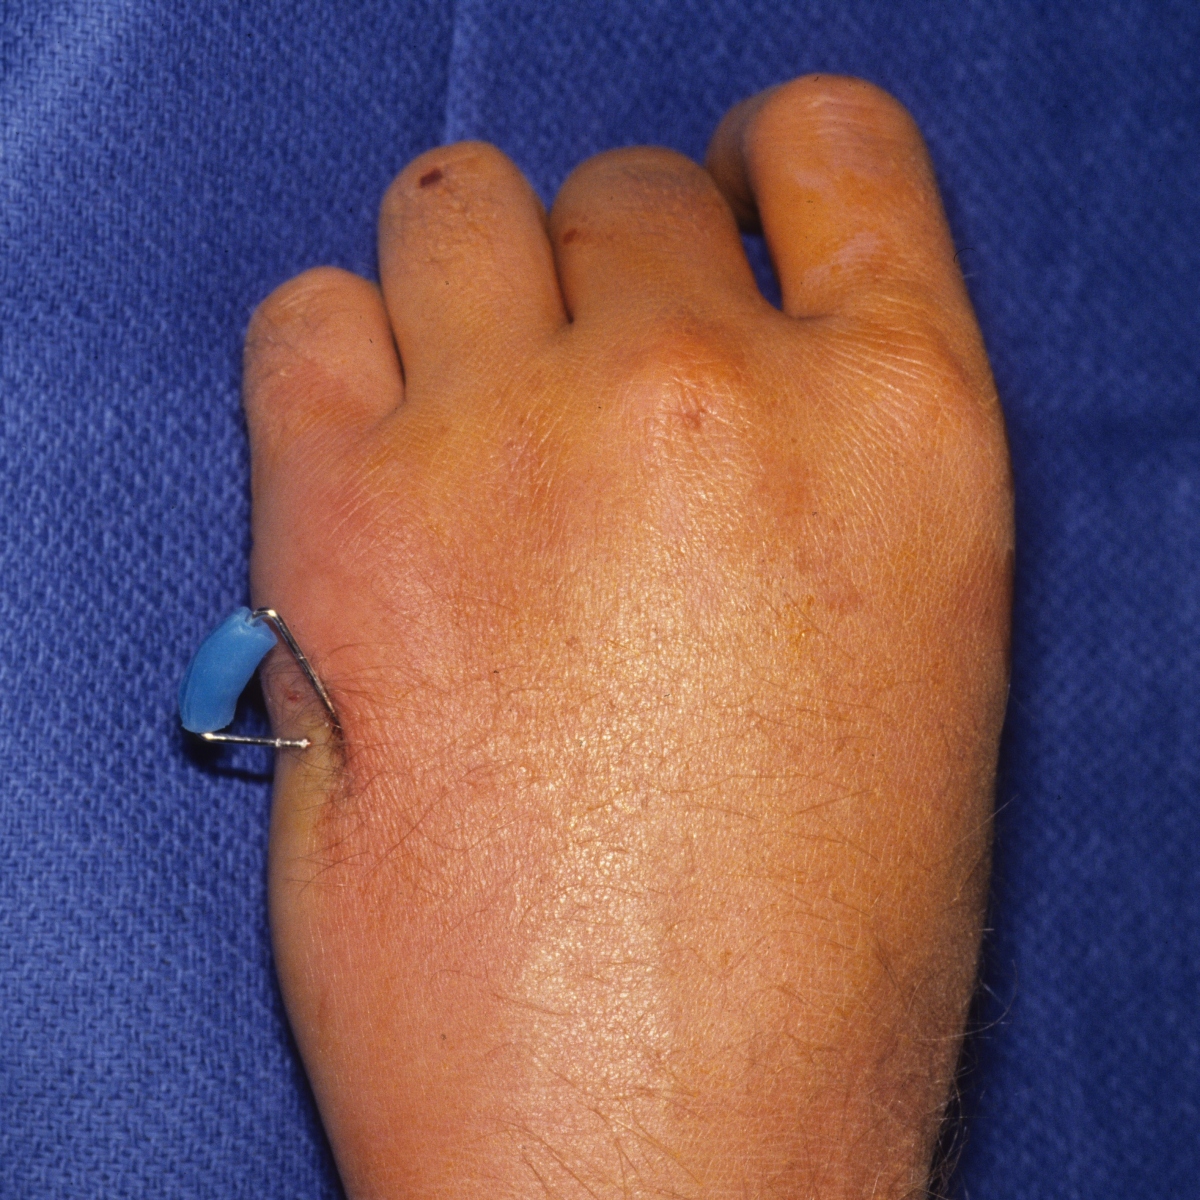

Carol lin, md & brad merk, md. There is at least a theoretically increased risk if reduction is determined to be adequate, then a guide pin may be placed through a percutaneous incision. With special reference to percutaneous knowles. Twenty three patients had other medical conditions. A femoral neck fracture most often results from a recent fall on the affected hip. Garden 1 fractures collapse less frequently than garden 2 fractures, but both have high rates of fracture collapse when treated to union with in situ percutaneous pin fixation. Femoral neck fractures close to the hip joint are easy to recognise. It is a fracture that is commonly found in older individuals who are suffering from osteoporosis and athletes. Displacement of femoral neck fracture will disrupt the blood supply and cause an intracapsular hematoma (effect is controversial). The femoral neck (femur neck or neck of the femur) is a flattened pyramidal process of bone, connecting the femoral head with the femoral shaft, and forming with the latter a wide angle opening medialward. There were 36 garden grade iii and 26 grade iv fractures. Treatment may consist of repair or replacement. Femoral neck fracture is a type of hip fracture common in elderly, osteoporotic women. Carol lin, md & brad merk, md. They generally lead to immediate immobility. The wire is driven into the femoral head. Femoral neck fractures are a subset of proximal femoral fractures.